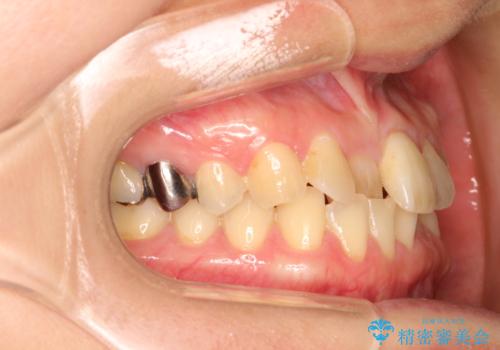

インビザラインにて矯正治療後の前歯のセラミッククラウン治療

- 前歯の歯並びが気になるとのことで来院されました。

右上の1番目の歯が内側に入り込んでしまっており、その歯がの先端がすり減ってしまっていました。

インビザラインによる矯正治療で前歯の歯並びを改善し、セラミッククラウン装着により歯の形態の回復をする計画としました。

矯正とセラミックを併用することで、より完成度の高い状態に仕上げることができました。